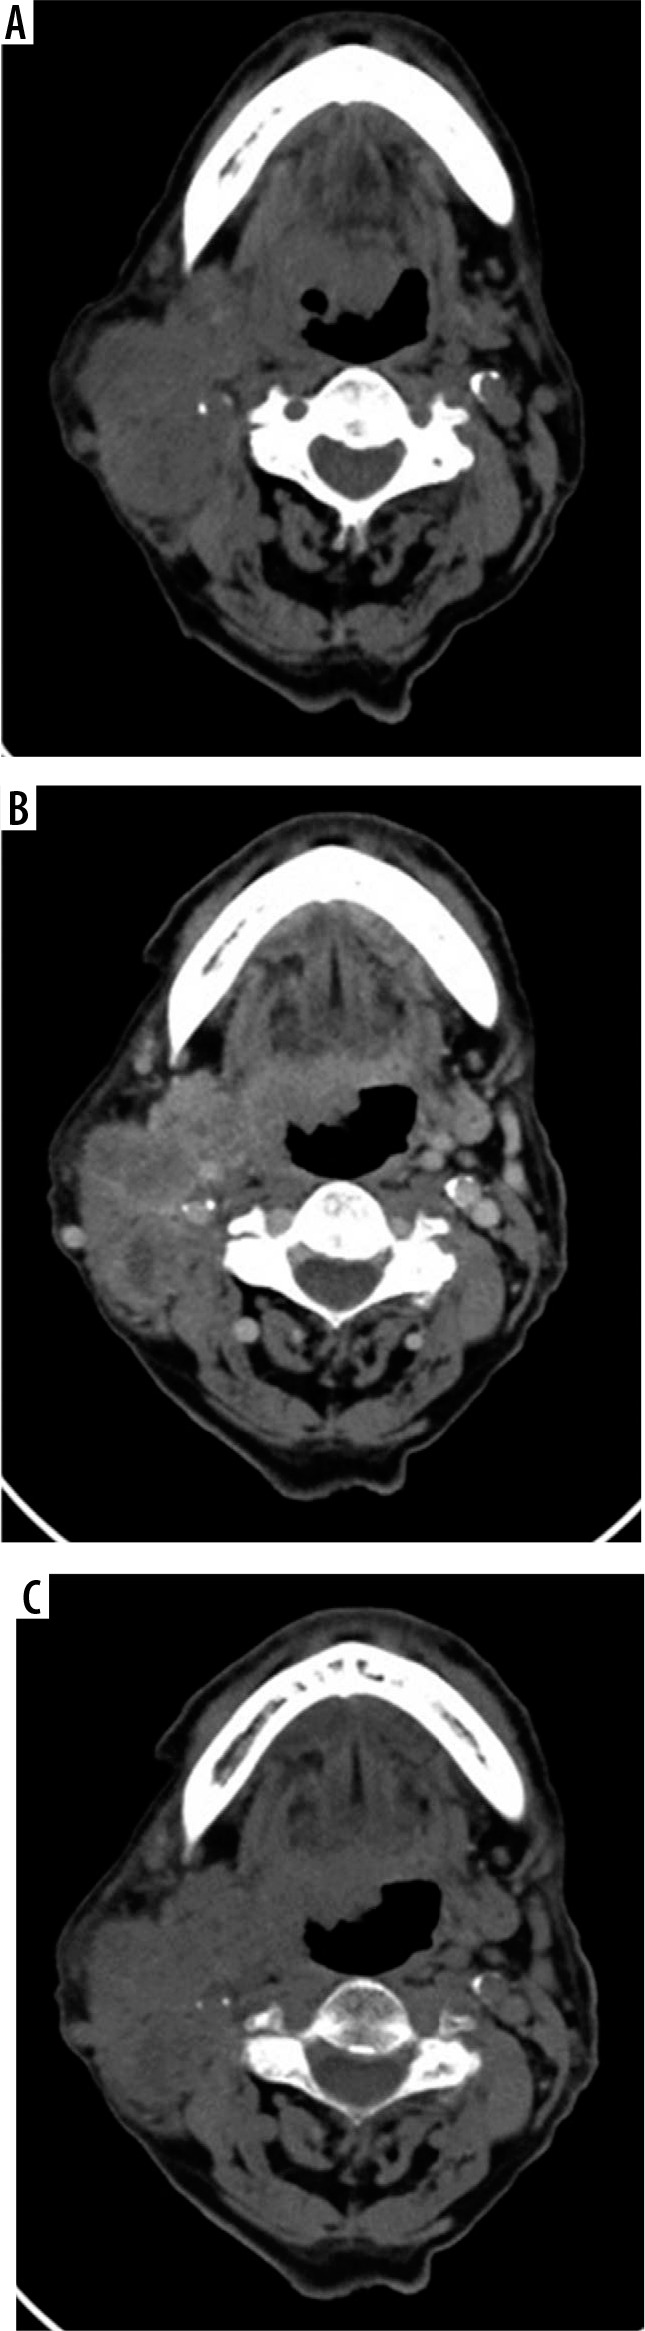

Figure 1

A 78-year-old woman with CA soft palate. A) Axial true noncontrast image was performed before intravenous contrast administration. B) Axial contrast-enhanced image was performed after intravenous contrast administration 70 seconds. C) Axial virtual non-contrast image was reconstructed due to iodine subtraction from the contrast-enhanced image by using postprocessing algorithms